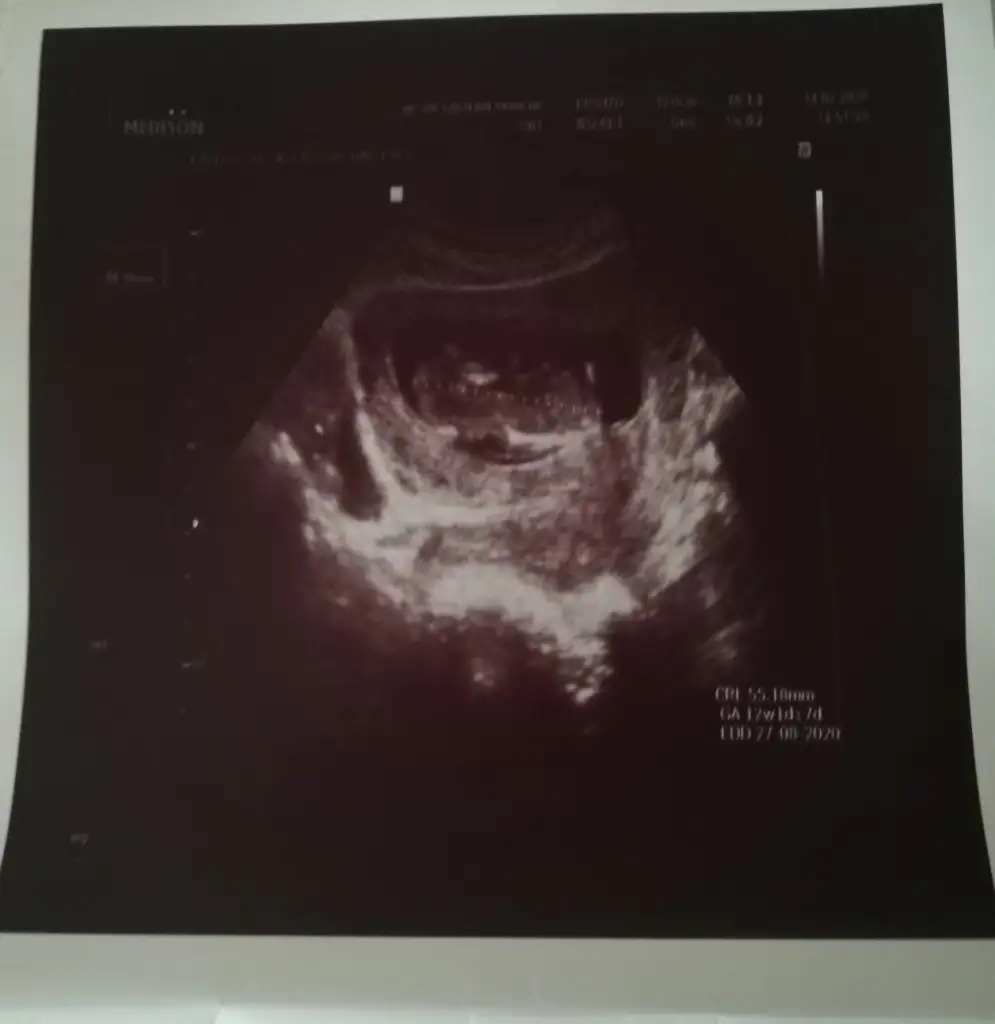

Tam net değil usg dr çıktısı yokmu bu usglerde emin olamadım sanki diyerek kız gibi gibi tekrar usg bekliyorum

Var tabiki ama ne olmadığı için ekran fotoğrafı yolladım